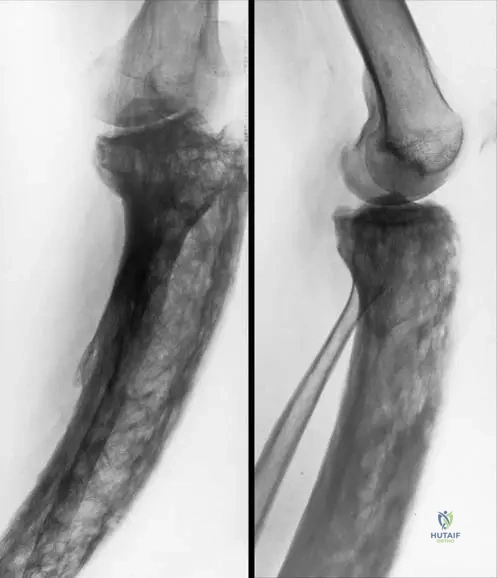

A 62-year-old male is diagnosed with monostotic Paget's disease affecting his right femur. Radiographs show a laterally and anteriorly bowed long bone. Histological examination of a bone biopsy from the affected area would most likely reveal which of the following?

Correct Answer: C

Rationale: The text states, "Bone changes in Paget’s disease are characterized by the development of “woven” bone and lamellar pattern of collagen." This is the hallmark histological finding. Option A is incorrect as the bone is abnormal. Option B describes osteomalacia. Options D and E are not characteristic histological features of Paget's disease.

A 71-year-old male presents with a 3-month history of dull aching pain in his right lower extremity. Physical examination reveals an enlarged and bowed right tibia. Radiographs confirm the presence of a "sabre tibia" deformity. What is the primary pathological process leading to the abnormal growth of the bone cortex in Paget's disease?

Rationale: The text explains, "In the active phase with high turnover, the abnormal osteoclast activity creates lytic cavities, and the consequent increased bone production by active osteoblasts produces abnormal growth of the bone cortex." This describes the coupled but disorganized remodeling process. Option A is incorrect because osteoclast activity is increased. Options B, D, and E do not accurately describe the primary pathological process in Paget's disease.